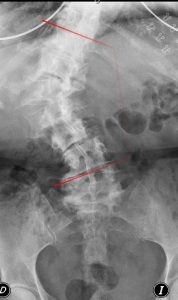

La escoliosis define la existencia de una desviación del eje de la columna en su plano coronal (una curvatura anómala de la columna vista de frente). Como las vértebras están articuladas, la rotación de las mismas también afecta el perfil (balance sagital) provocando a menudo una espalda plana.

La escoliosis comporta siempre una distribución de cargas “asimétrica” en la columna: en el lado cóncavo se aumentan las exigencias en compresión axial (formación de hueso) mientras que en al lado convexo se le “sobreexige” en distracción (distensión de ligamentos y articulaciones).